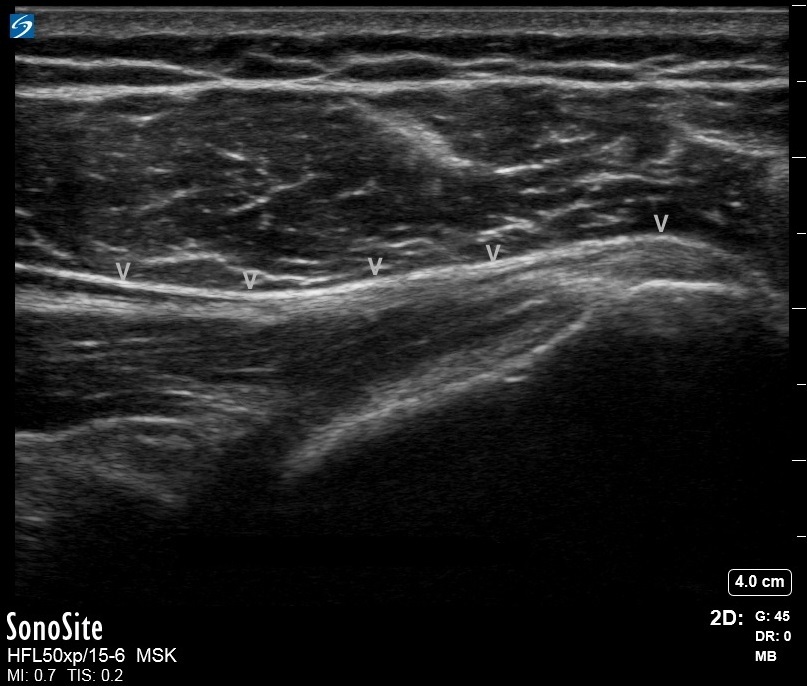

肩通常大円マイナー腱挿入画像